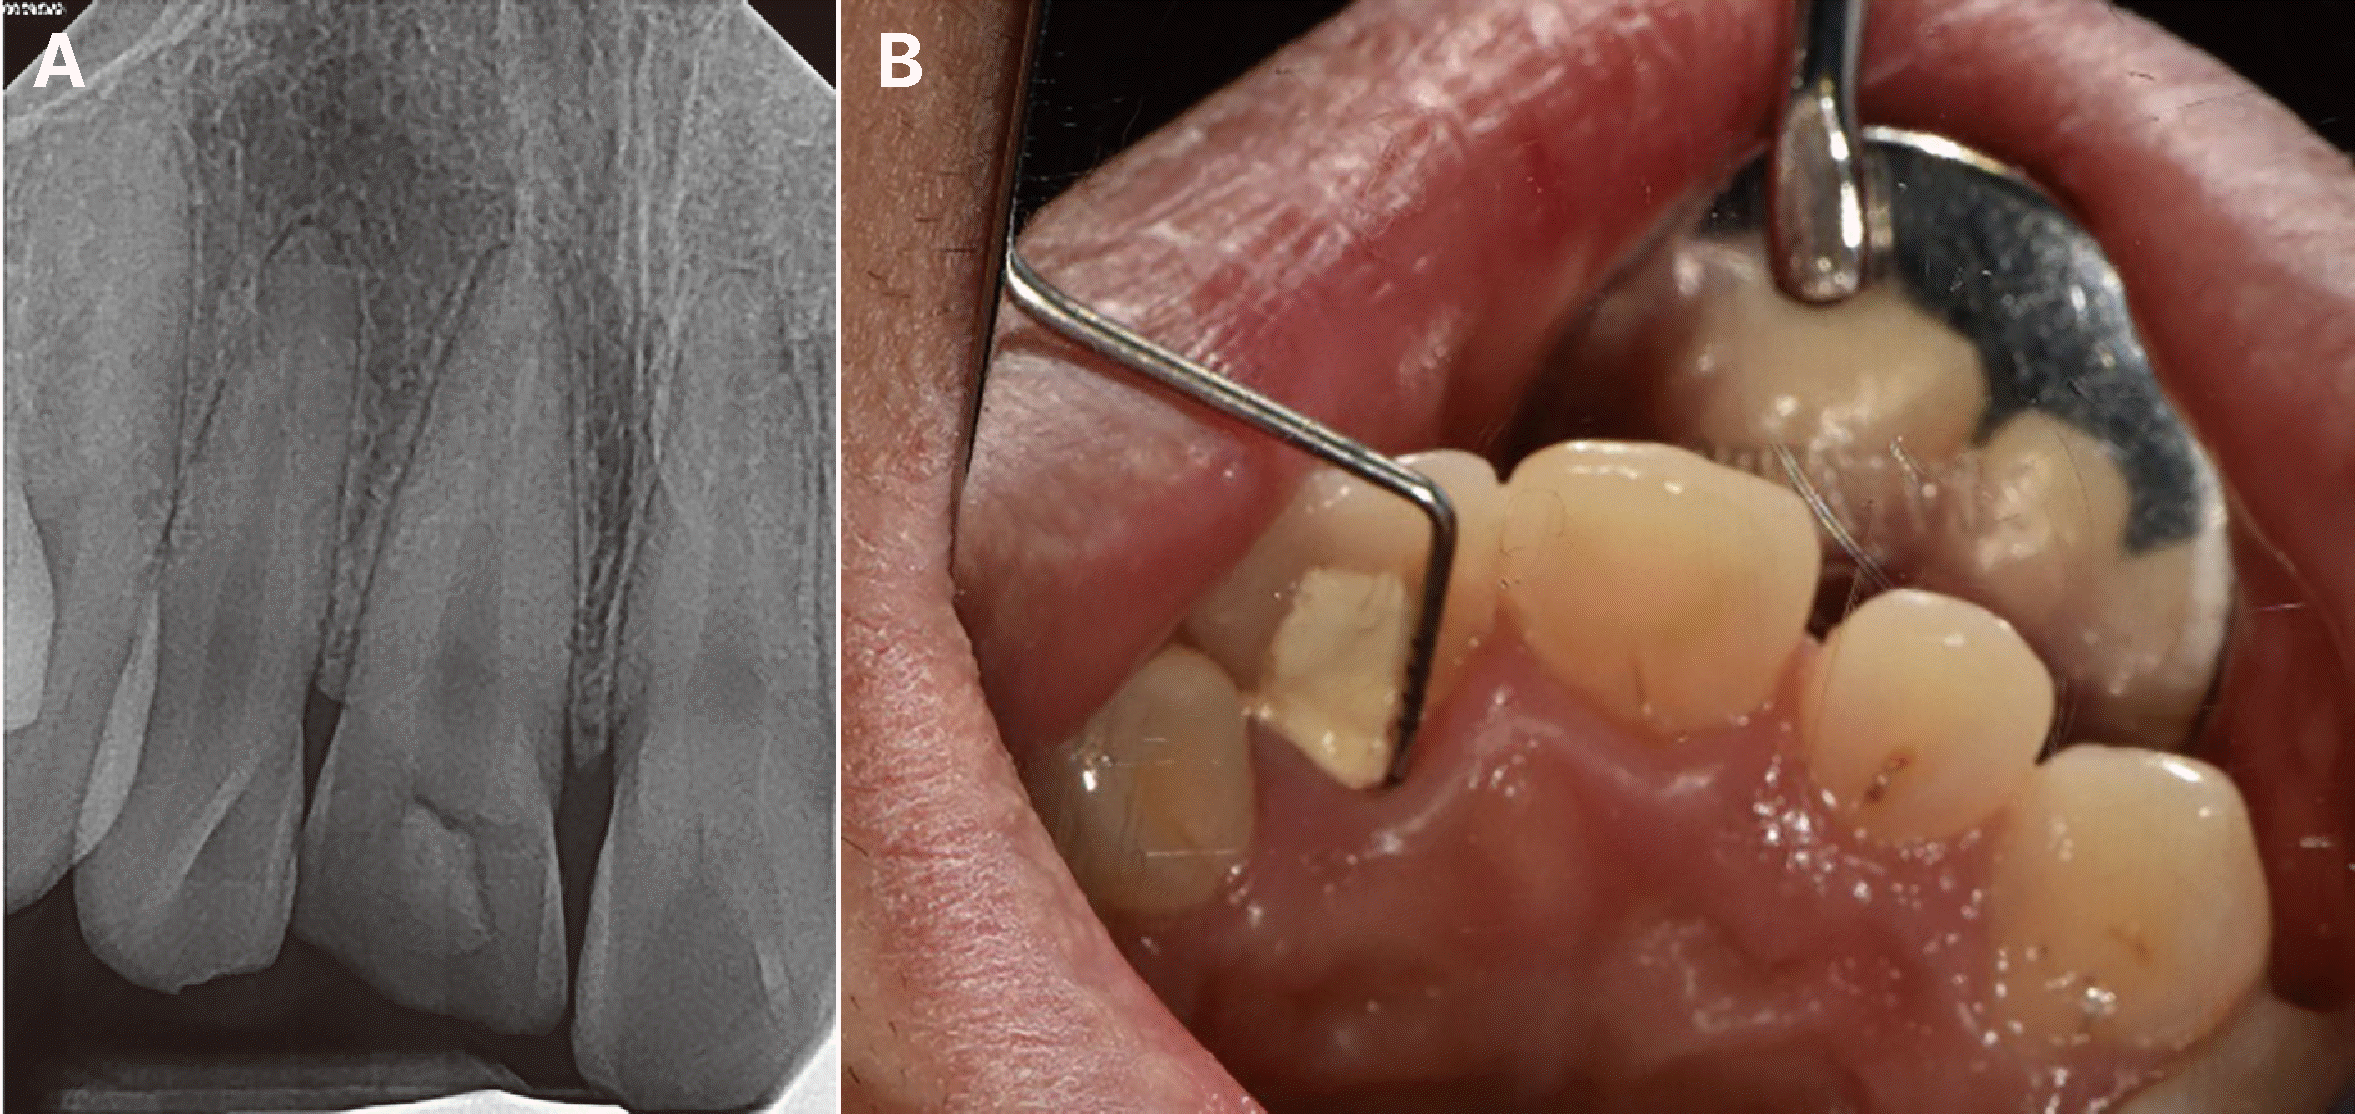

재식 1주 후 치은유두 봉합사를 제거하였으며 재식 2주 후 근관 평가를 시행하였다. 상악 양측 견치에 클램프를 적용하여 격리를 시행하고 협측에 수경성 임시충전재와 레진으로 이중 가봉해둔 임시재료를 제거하여 근관 내로 접근하였다. 수산화칼슘 첩약제를 제거하고 근관 세정을 시행한 후 페이퍼 포인트를 이용해 근관 건조가 잘 되는 것을 확인하였다. 거타퍼챠 콘(DiaDent, Cheongju, Korea) 및 실러(AH Plus sealer, Dentsply Detrey GmbH, Konstanz, Germany)를 사용하여 열연화가압충전(Continuous wave technique)으로 근관 충전을 시행하였다. 근관 와동 부위는 복합레진(LuxaCoreZ Dual shade A3; DMG GmbH, Eldgaustrabe, Hamburg, Germany)으로 충전하였다(Fig. 3). 재식 3주 후 동요도가 감소하여 레진-강선 고정을 제거하였다. 전치부 치은이 완전히 치유되고 연조직 뿐만 아니라 경조직의 치유가 진행이 될 때까지 임시치아 상태로 8주간 경과관찰을 시행하였다.